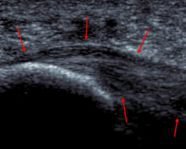

At The London Podiatry Centre, we combine advanced biomechanical assessment, computerised gait analysis, and high-resolution diagnostic ultrasound to quickly and accurately identify the specific cause of heel pain. Many heel problems are rooted in underlying biomechanical dysfunction, which may lead to ongoing strain and prevent healing if not properly addressed.

Full integration of biomechanical gait analysis and diagnostic ultrasound into every patient assessment.